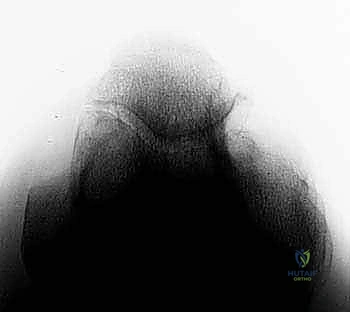

* الأشعة السينية (X-rays): ضرورية جداً لرؤية النتوءات العظمية (Osteophytes) في الناتئ المرفقي، وتضييق مساحة المفصل.

* التصوير بالرنين المغناطيسي (MRI): يُستخدم لتقييم الأنسجة الرخوة، وتحديداً حالة الرباط الجانبي الزندي (UCL)، والكشف عن وذمة نخاع العظم (Bone Marrow Edema) الناتجة عن الاصطدام المتكرر، وتقييم حالة الغضاريف.

* الأشعة المقطعية (CT Scan): في بعض الحالات المعقدة، تُستخدم لبناء نموذج ثلاثي الأبعاد للمفصل للتخطيط الجراحي الدقيق قبل إدخال المنظار.